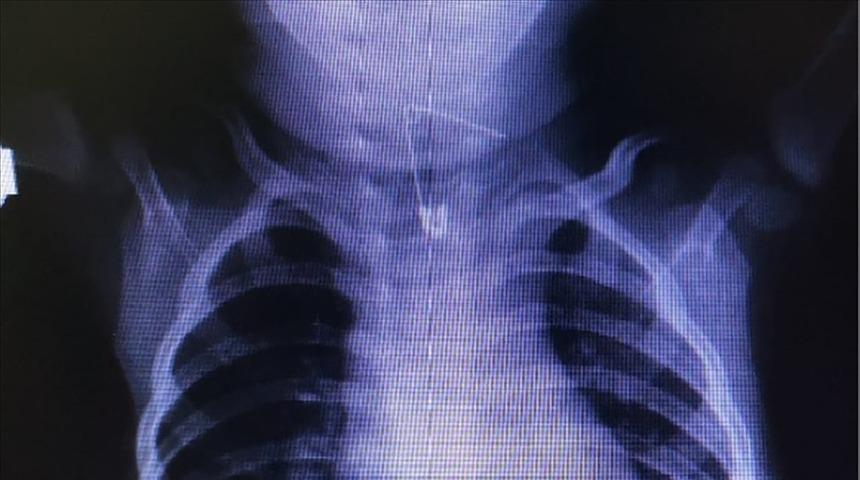

Bebeği muayene eden Çocuk Sağlığı ve Hastalıkları Uzmanı Dr. Bayram Kuratmer, yabancı cisim yuttuğundan şüphelenerek röntgen çektirdi. Röntgende, bebeğin çengelli iğne yuttuğu tespit edildi.

Yemek borusuna saplanan iğne, Başhekim ve Göğüs Hastalıkları Uzmanı Opr. Dr. Ali Hikmet Karan tarafından endoskopik yöntemle çıkarılarak bebek sağlığına kavuşturuldu.